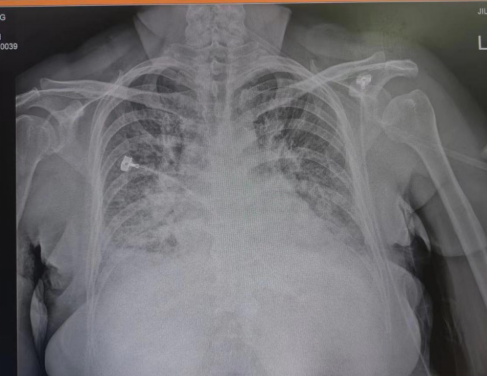

术前检查

患者刘女士因呼吸困难于我院门诊就诊,就诊时出现急性呼吸困难表现,端坐呼吸,由急诊转入重症监护病房。经吉心医生全面检查,明确患者为缺血性心肌病,急性冠脉综合征导致慢性心衰急性加重,急性肺水肿,并二尖瓣大量返流,情况十分危急。